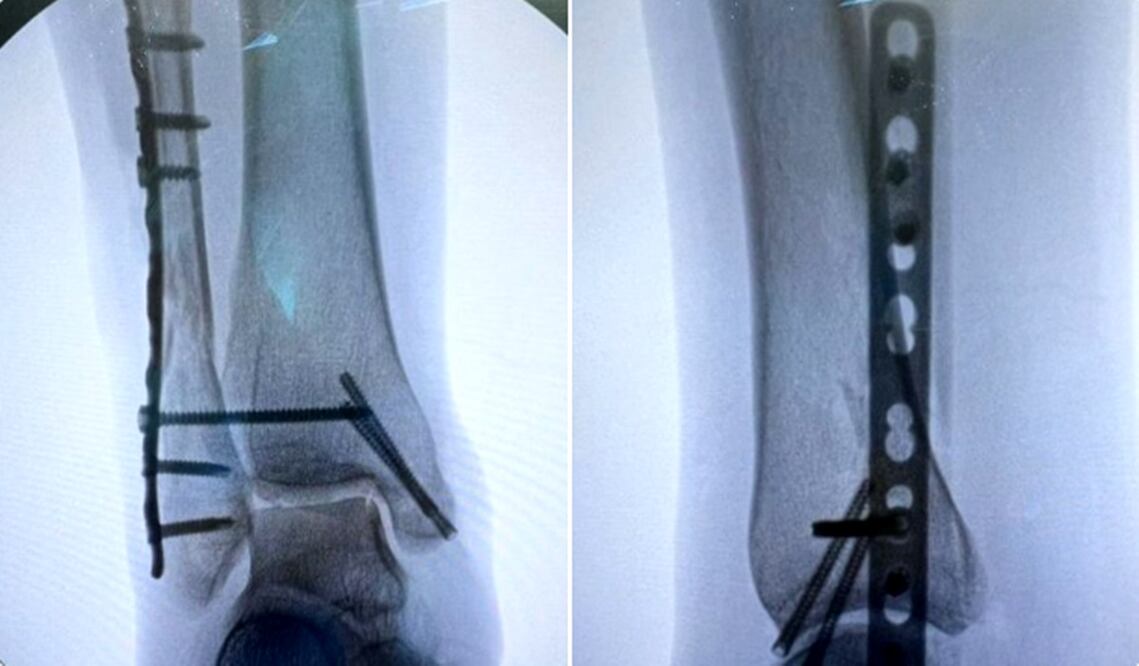

Laura Ballesteros Mancilla, senadora y coordinadora de campaña del candidato presidencial de Movimiento Ciudadano, Jorge Álvarez Máynez, relató en la red social X que la cirugía salió bien; detalló que el pie se había separado del tobillo por la caída, durante la tragedia ocurrida en San Pedro, Nuevo León, y que estará tres meses en recuperación.

Dio a conocer que sigue hospitalizada, pero que hoy la dan de alta; asimismo mencionó que la cirugía a la que fue sometida salió bien, “el pie se había separado del tobillo por la caída” y dijo que estará tres meses en recuperación.